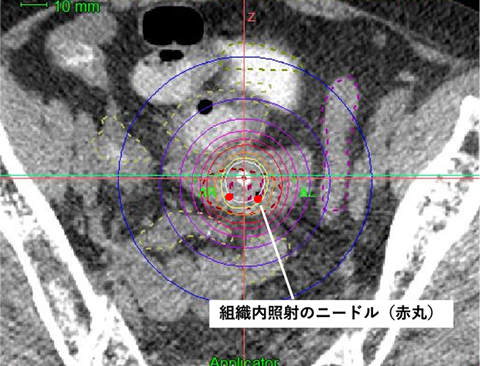

従来は2方向からのレントゲン撮影による2次元治療計画が行われていましたが、現在、当院ではアプリケーターを挿入したままCT画像を撮影できます。この画像を使って、3次元治療計画を行うI G B Tを実施しています。

レントゲンよりも臓器が見えるため、腫瘍にしっかりと放射線を照射しながら、正常臓器の線量を低減することが可能です。

組織内照射とは、腫瘍の内部やその周囲に専用の細いニードル(径約2mm)をCT画像誘導下に直接刺入し、そのニードルを通して放射線を照射する治療法です。